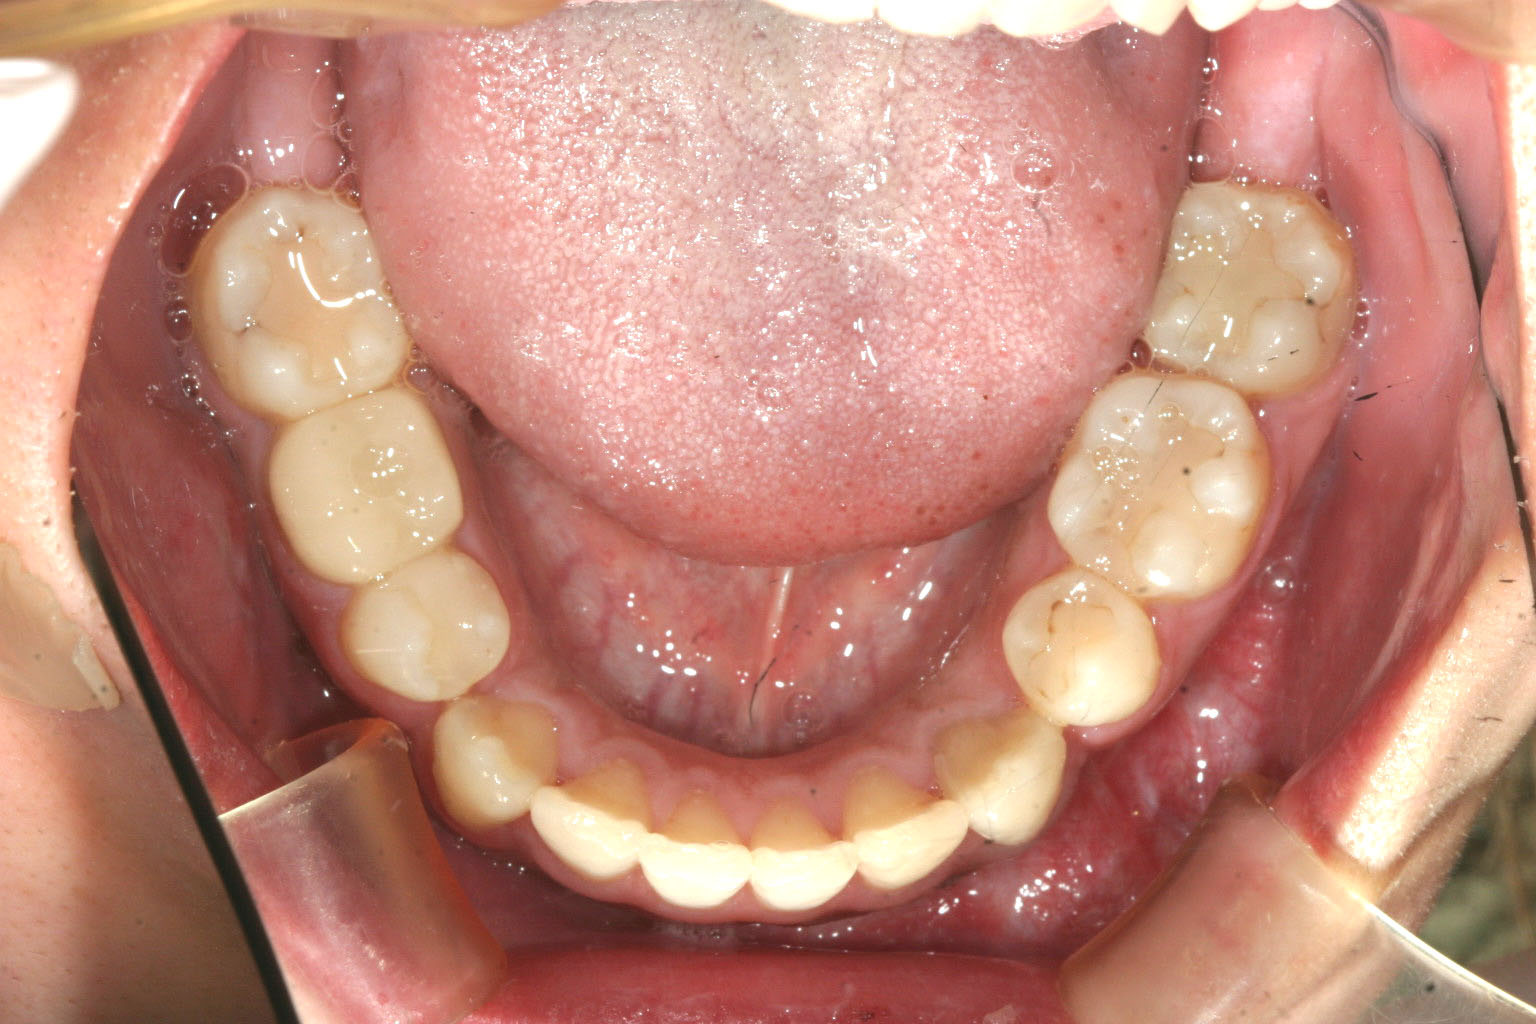

下顎も外科後に残った少しのスペースを閉じるのと叢生の治療です。 綺麗に改善してます。

下顎を切断してメタルでつないであるのが見受けられます。